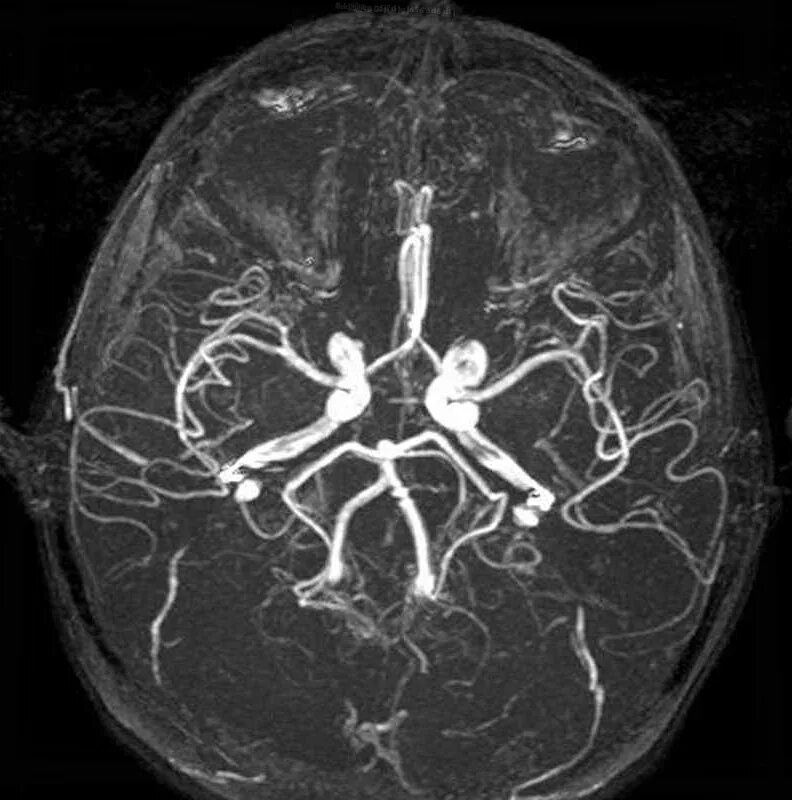

Мрт с контрастированием головного